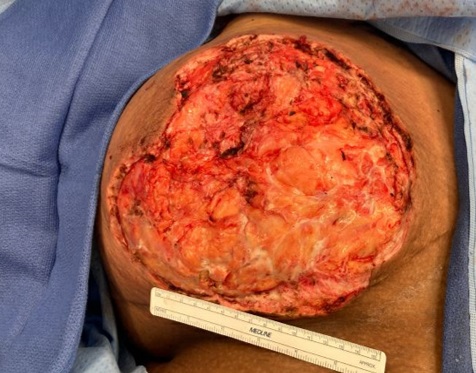

Clinical images

Contributed by Ayesha Farooq, M.B.B.S. and Julie Jorns, M.D. (Case #515)

Images hosted on other servers:

Gross description

- Excisions rare; specimens usually from incision and drainage procedures and typically received in fragments